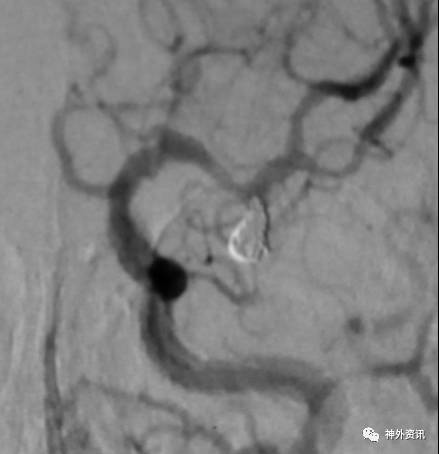

A1起始段动脉瘤,微导管成袢逆行到位